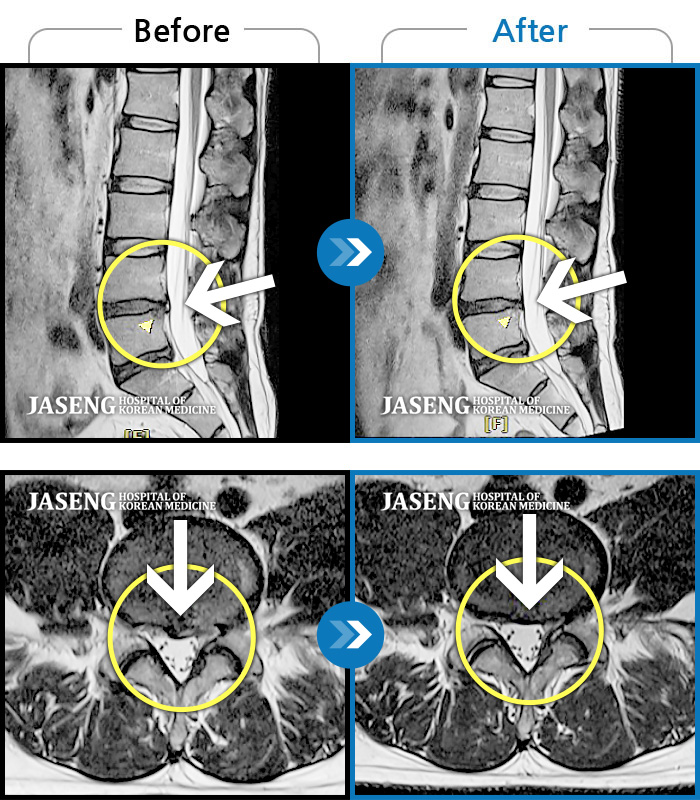

허리디스크

광주 · 장영우 원장

허리 양측부터 골반까지 통증, 우측 하지 외측으로 이어지는 저린감

촬영시기

2020.11.12 ~ 2021.10.18

2021.10.22

조회수 3,962